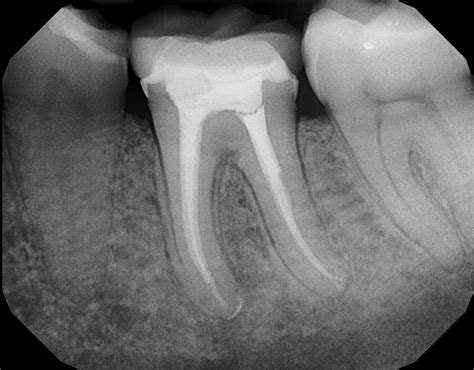

1. Diagnosis and X-rays: Your dentist will take X-rays to see the shape of the root canals and determine if there are signs of infection in the surrounding bone.